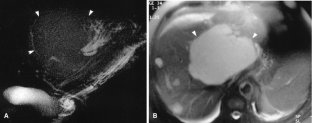

Usual and unusual causes of extrahepatic cholestasis: assessment with magnetic resonance cholangiography and fast MRI

Cholestasis may result from hepatocellular (intrahepatic) disease or biliary tract (extrahepatic) abnormalities. Etiologies causing extrahepatic cholestasis are extremely diverse and invasive procedures, such as endoscopic retrograde cholangiopancreatography (ERCP) and percutaneous transhepatic cholangiography (PTC), were previously required to establish the diagnosis. Due to refinements of magnetic resonance imaging (MRI) techniques, the patient with extrahepatic cholestasis currently can be evaluated noninvasively, and the information revealed frequently exceeds the findings obtained by ERCP and PTC. In this essay, we illustrate the classic MR cholangiographic (MRC) and MRI features of a variety of disorders causing extrahepatic cholestasis, including non-neoplastic disorders of the biliary tract (congenital abnormalities, infectious processes, iatrogenic disorders, and postsurgical complications) and neoplastic conditions (e.g., tumors of the pancreas, biliary tree, liver, ampulla, and regional lymph nodes). In most cases, familiarity with the key MRC features in addition to information obtained via cross-sectional MR images provide sufficient information for adequate lesion characterization.